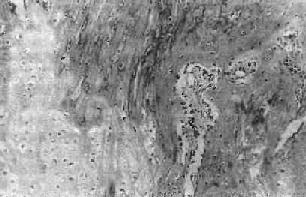

图17-2 骨痂

在幼稚编织骨骨小梁表面的骨母细胞排列成行